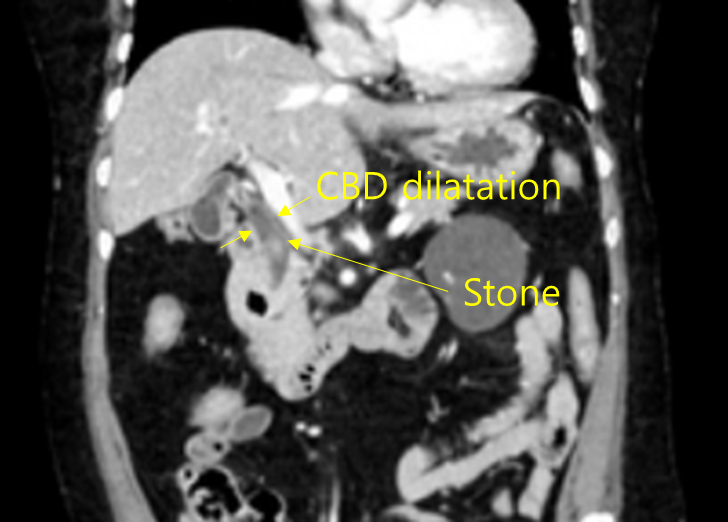

75세 여자가 1일 전부터 윗배가 아파서 응급실에 왔다. 10년 전부터 당뇨병과 고혈압으로 투약 중이다. 열감이 있고 오한이 들며 식욕도 없다고 한다. 혈압 125/80mmHg, 맥박 90회/분, 호흡 20회/분, 체온 38.2℃이다. 의식은 명료하며 윗배에 압통이 있다. 혈액검사 결과는 다음과 같다. 복부 컴퓨터단층촬영 사진이다. 응급실에서 광범위 항생제를 투여하였다. 다음 치료는?

백혈구 14,500/mm3, 혈색소 11.5.g/dL, 혈소판 198,000/mm3, 아스파르테이트아미노전달효소 320U/L, 알라닌아미노전달효소 355U/L, 알카리인산분해효소 652U/L, 감마글루타밀전달효소 457U/L, 알부민 4.5g/dL, 총빌리루빈 4.1mg/dL, 직접빌리루빈 2.8mg/dL, C-반응단백질 18.0mg/L(참고치, <10)

Img | CT: 담관 확장, 담관내 담석 |

윗배 통증을 주소로 내원한 환자로, 발열과 함께 혈액검사 상 담즙정체를 시사하는 빌리루빈, AST/ALT, ALP/GGT의 상승이 확인되므로 급성 담관염을 의심할 수 있다. 복부 CT에서도 담관 확장 및 담관내 담석이 확인되므로, 담석에 의해 급성 담관염이 발생한 것으로 추측된다. 치료로는 담석 제거를 위해 내시경역행쓸개이자조영술(ERCP)로 팽대근절개술을 시행하여야 하겠다.

진단 | • US/CT: Bile duct dilatation, stone이 보일 수도 있음 • MRCP/ERCP: Proximal bile duct dilatation, filling defect 등 |